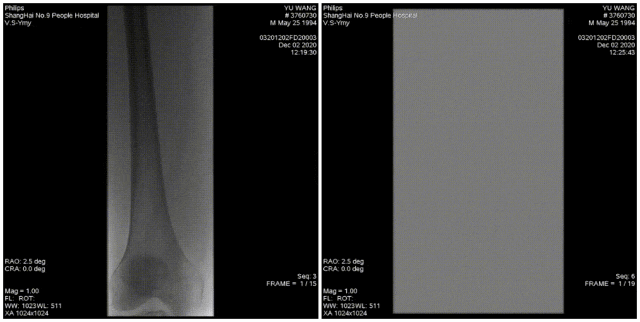

图:术前

图:4mm和3mm球囊扩张腘和胫后动脉

图:术后